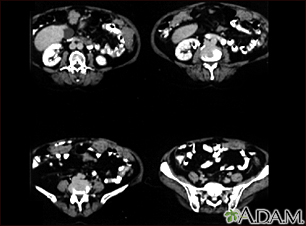

Mediphany How to read an MRI or CT scan

Abdominal CT scan Information